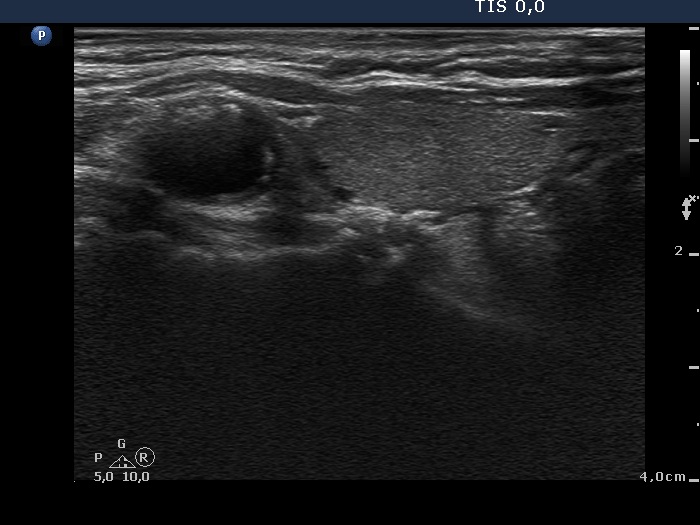

Ultrasonography. The thyroid was minimally hypoechogenic. There was a discrete lesion in the upper part of the right lobe. It was equivocal whether this echo abnormality was a nodule or not. A relatively large hypoechogenic, inhomogeneous nodule was in the lower half of the right lobe. This nodule did not present halo sign, but did a perinodular blood flow.